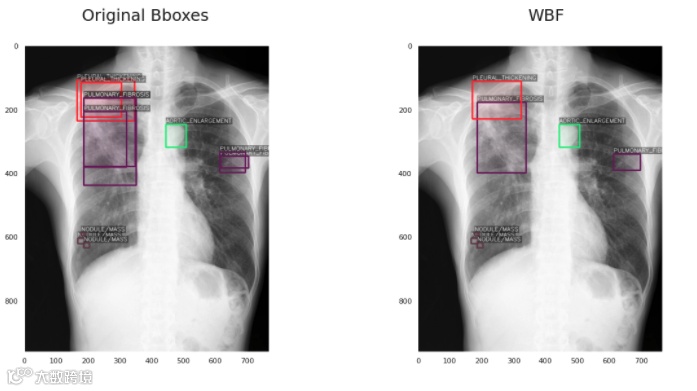

5、加权框融合(WBF)后处理,0.226 mAP (+15%)

这对我来说也是一个全新的想法,在网上很难找到。加权框融合是一种对目标检测模型产生的框进行过滤,从而使结果更加准确和正确的技术。它的性能超过了现有的类似方法,如NMS和soft-NMS。具体内容我会在另一篇文章介绍。应用WBF的结果是这样的: